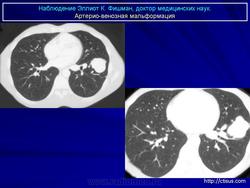

Легочные артерио-венозные мальформации.

1.malf_.slayd39.jpg